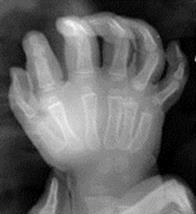

Функция кисти нарушается. Возникает косметический дефект. Сращение может быть мягкотканным, если сращены только мягкие ткани, и костным. Сращение нормально развитых пальцев называется простой формой синдактилии.

Рис.6. Простая форма синдактилии.